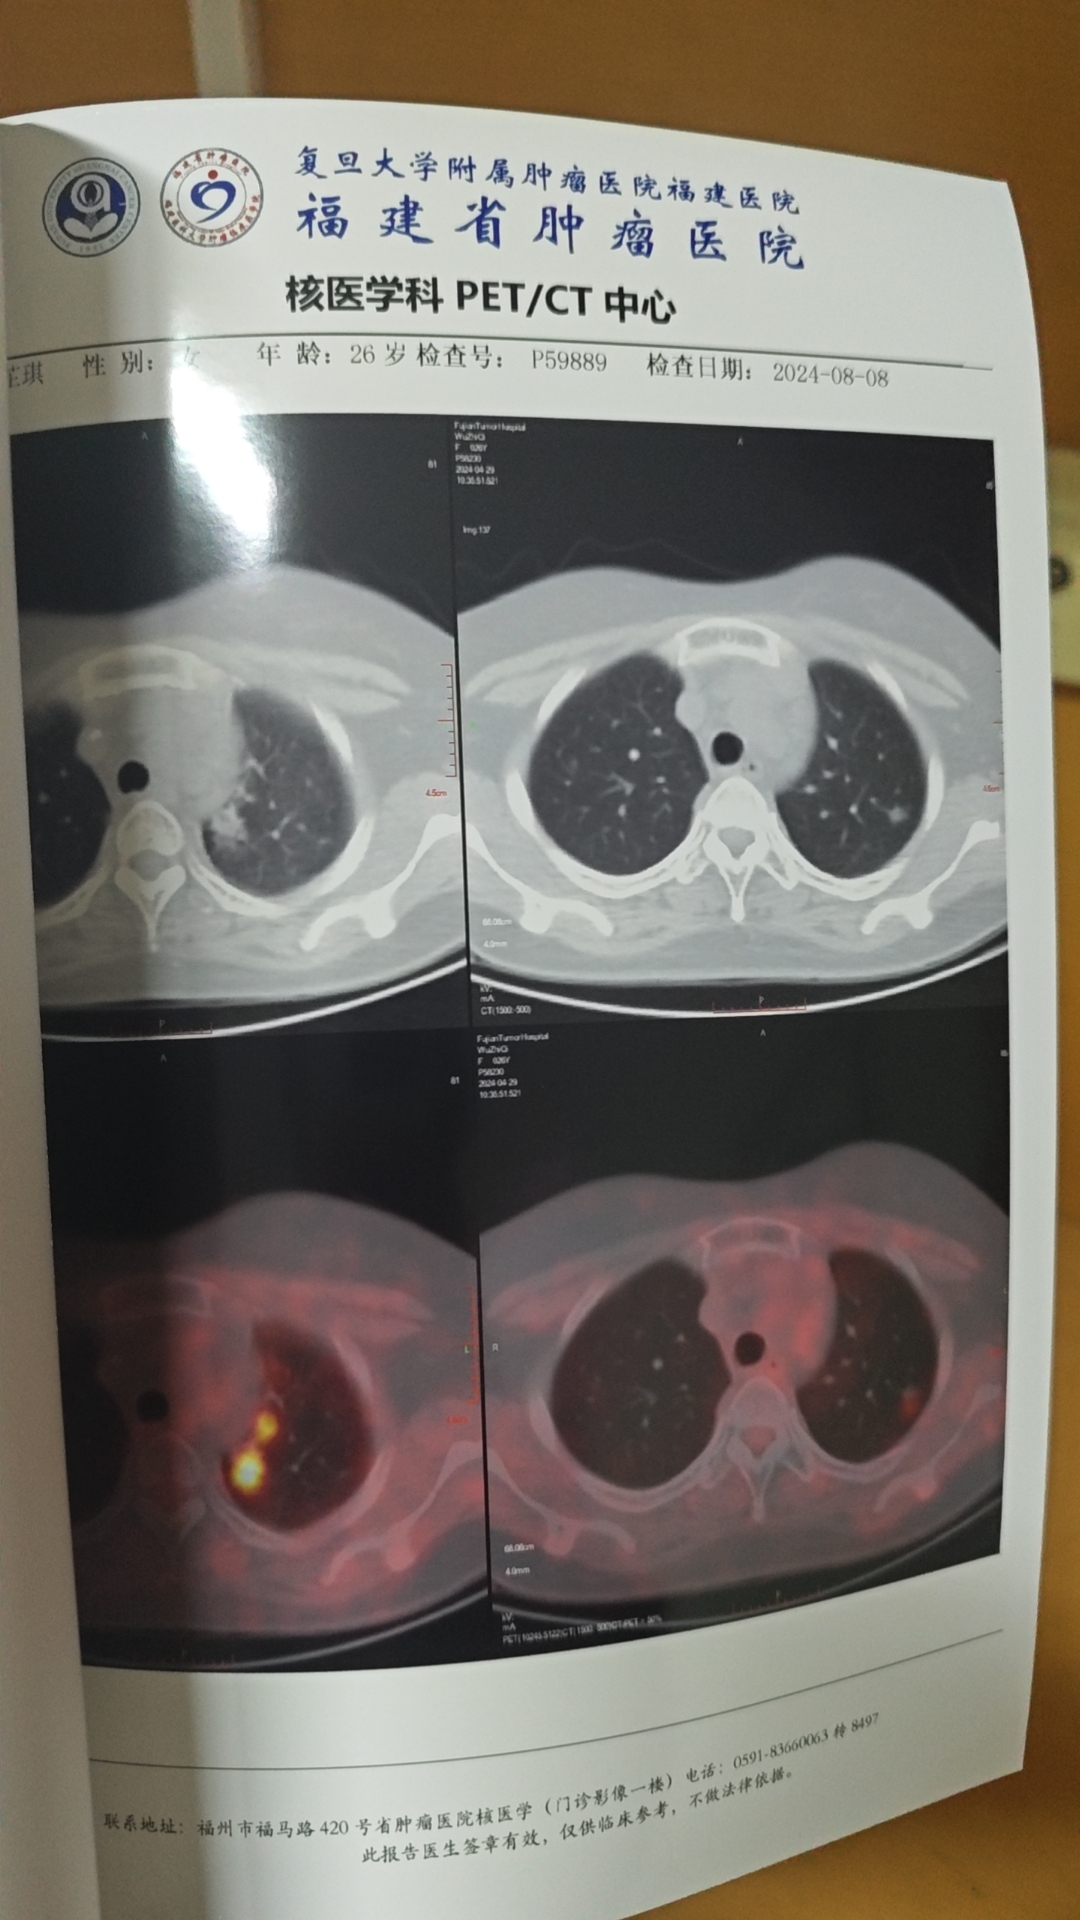

附图按时间排序分别为:中期评估的胸部平扫,四个疗程两周多后的pet报告,以及四疗后一个月胸部平扫。

最新一次pet显示肺上部有结节影,附图,左边为最新一次pet,右边是四月底的。

挂了十天消炎药,胸部平扫显示仍有结节影。最后1p是特写